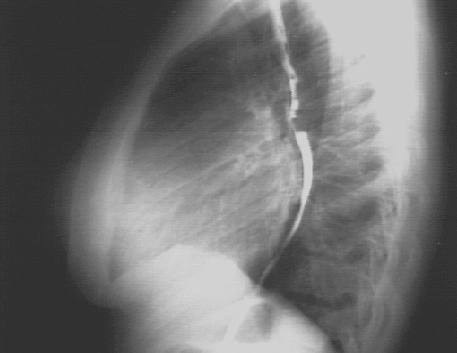

Lateral view

The markedly enlarged left atrium is manifested by the double contour within the heart border, an elevated left mainstem bronchus, and an enlarged left atrial appendage. The lateral view with barium swallow, demonstrates posterior displacement of the esophagus by the markedly enlarged left atrium.